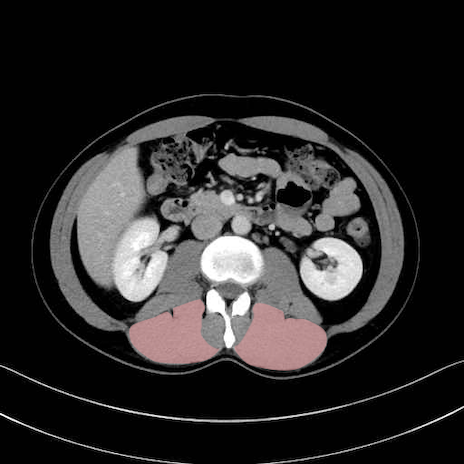

脊柱起立筋 (Erector spinae)

多裂筋 (Multifidus)